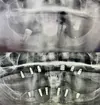

Implant tedavisi